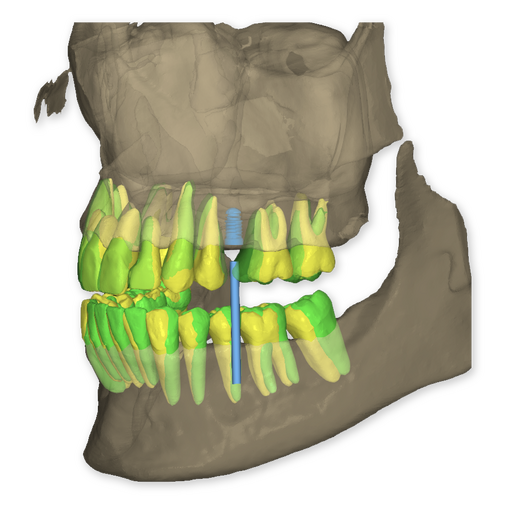

The DSD Interdisciplinary is a digital wax up of the upper and lower arches, designed considering a facially-driven, clinical and functional analysis of the patient.

It is our most comprehensive planning option, and includes all the 3D treatment simulations needed for each case, such as ortho, perio, implants, grafts and orthognathic surgery.

Our 3D simulations showcase facilitate a deeper understanding of the required procedures. This leads to the creation of a broader treatment plan and enables a more efficient communication with your patients.